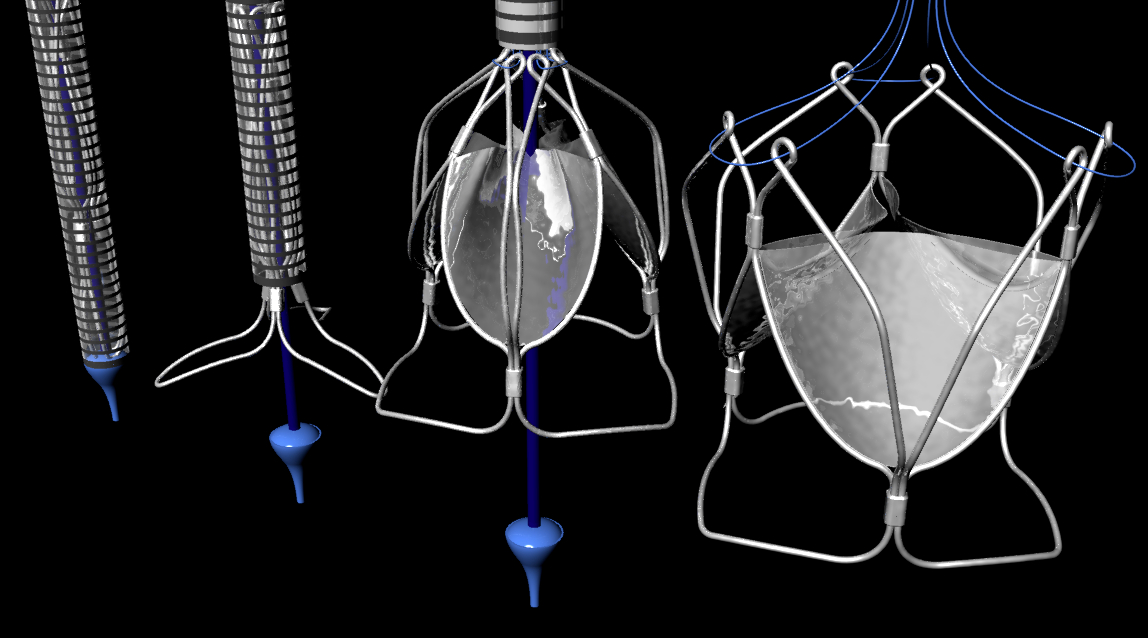

Transcatheter aortic valve implantation (TAVI) is a great alternative treatment option in high surgical risk and inoperable patients with severe symptomatic aortic stenosis (AS). TAVI is a rapidly emerging technique with a constantly expanding body of evidence. However, the devices, which are commercially available and are currently used widely, have several major limitations. In particular, the inability to reposition/ retrieve/ resheath valves, in addition to several patient selection and procedural limitations, such as the occurrence of moderate to severe paravalvular regurgitation (PVR), the risk of annular rupture, atrioventricular (AV) conduction abnormalities with subsequent pacemaker requirement, vascular complications and associated bleeding, coronary ostial obstruction by the valve, stroke, as well as complex delivery processes, are expected to be overcome with the newer generation valves. Consequently, a number of new transcatheter valve choices have been developed either for clinical study or are in the pipeline, that it is hoped to bring meaningful clinical outcomes compared with the currently commercially available technology. Early data on design modifications have shown significant reductions in adverse outcomes from TAVI.